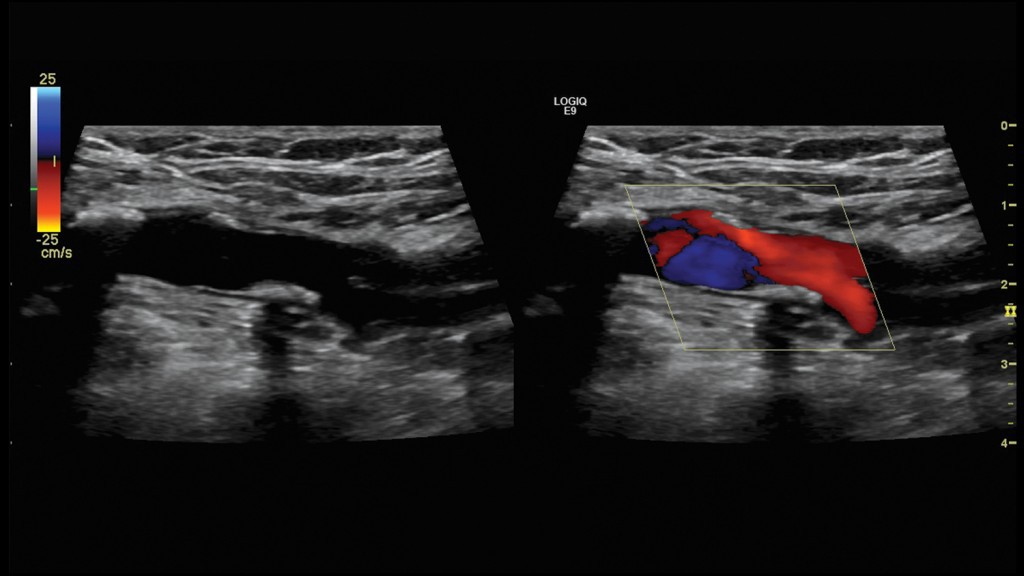

其一,實時四維成像技術 可進行超聲四維重建,尤其在胎兒畸形篩查方麵有重大意義,容積探頭表麵成像模式對胎兒體表結構進行重建或實時三維、四維成像,可清晰觀察二維超聲無法顯示的胎兒表麵結跑結構及其相互間的空間位置關系,可以發現胎兒的一些生理變異和畸形,可觀察胎兒骨骼系統的生長發育情況,有助於發現一些先天性畸形,可對胎兒彩色多普勒血流進行四維重建,可診斷臍帶和胎兒血管的畸形。四維成像對於婦科囊性及實性腫瘤可清晰的現實腫瘤內壁和包膜是否平滑,有無贅生物,及其大小和形態特征,對臨床醫師手術方案的製定提供可靠的依據。此外對於卵泡形態的觀察和容積的測量,可監測卵泡的發育,準確預測排卵。對於膽囊、膀胱、胃腸道等空腔臟器在充液狀態下可良好的顯示其內部結構和病變特征,觀察結石、息肉、腫瘤潰瘍等病變的立體形態,彌補瞭二維超聲的不足,對定性和定位診斷有極大的幫助。對於血管的四維重建,可清晰完整的顯示斑塊的大小及形態,並可多角度的觀察斑塊的形態及內膜情況,並可清晰顯示血管的主乾及分支,所獲得的病變信息更接近於實際解剖結構。

組織彈性成像技術和寬景成像技術。組織彈性成像可有效鑒別實質性腫瘤的良惡性,對惡性病變診斷具有較高的特異性和敏感性,可用於乳腺、前列腺、甲狀腺等小器官,另外組織彈性成像還可用於肝纖維化的診斷、局部心肌評價。